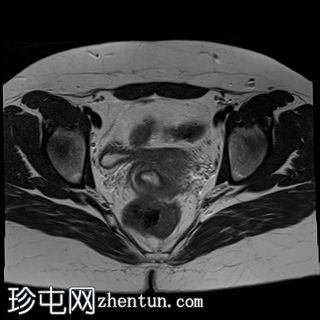

轴位

T2加权像

双侧卵巢位置接近(卵巢相吻),左侧卵巢内可见一边界清晰的囊性病变,大小约3.1 × 2.7 × 2.9 cm,T1加权像呈高信号,T2加权像可见暗点征及内部暗点征。以上MRI特征符合卵巢子宫内膜异位囊肿的诊断。

右侧卵巢可见一囊肿,大小约为 2.8 × 2.0 × 2.2 cm,T1 加权像呈高信号,囊内可见液-液平面,提示囊内含有不同时期的出血性物质。由于对侧卵巢存在典型的子宫内膜异位囊肿,且该囊肿无强化,影像学表现强烈提示为另一子宫内膜异位囊肿。

双侧卵巢均可见多个小卵泡。

双侧卵巢囊性病变,MRI 表现符合子宫内膜异位囊肿的特征,左侧较大。未见强化壁结节或实性成分,提示无恶性转化。